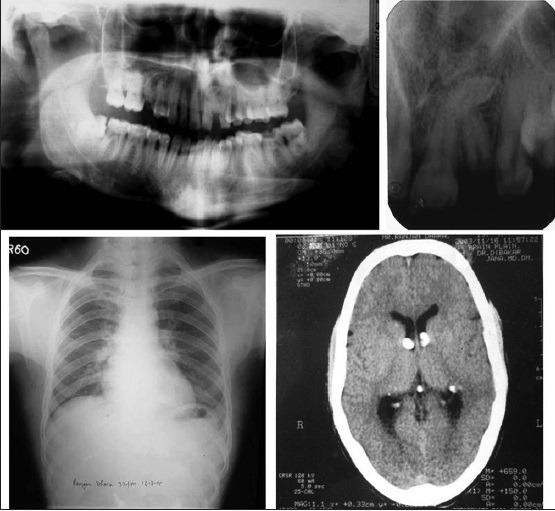

Tuberous sclerosis complex is an unusual autosomal dominant neurocutaneous syndrome characterized by the development of benign tumors affecting different body systems affecting the brain, skin, retina, and viscera. It is characterized by cutaneous changes, neurologic conditions, and the formation of hamartomas in multiple organs leading to morbidity and mortality. The most common oral manifestations are fibromas, gingival hyperplasia, and enamel hypoplasia. The management of these patients is often multidisciplinary involving specialists from various fields. Here, we present a case report of a 26-old-year male patient with characteristic clinical, radiological, and histological features of tuberous sclerosis complex.

结节性硬化症是一种罕见的常染色体显性神经皮肤综合征,其特征是在影响大脑、皮肤、视网膜和内脏的不同身体系统中出现良性肿瘤。它的特点是皮肤改变、神经系统疾病以及多个器官中错构瘤的形成,从而导致发病和死亡。最常见的口腔表现是纤维瘤、牙龈增生和釉质发育不全。这些患者的治疗通常需要多学科参与,涉及各个领域的专家。在此,我们报告一例26岁男性患者,具有结节性硬化症的典型临床、放射学和组织学特征。